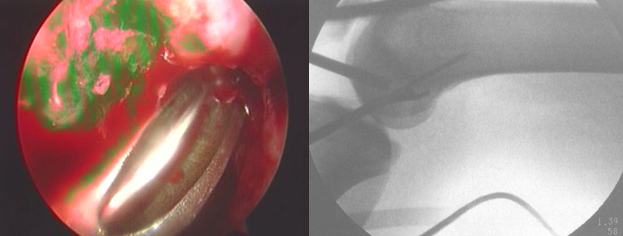

关节镜下观

正常前交叉韧带

前交叉韧带损伤后形成的疤痕组织

ACL定位器

准确放置ACL定位器

股骨导针为直径1mm克氏针

钻胫骨导针

在导针引导下制作胫骨骨道

股骨定位器与股骨导针

准确放置股骨定位器

按照左膝1点、右膝11点 (髁间窝后顶为12点)定位的基本方法定位,在能够保证骨道后壁完整的前提条件下,尽可能向后接近过顶处。

股骨引导器引导下,钻股骨导针

制作股骨隧道

股骨骨道深度一般为:2.2~2.7cm

清理骨道内残渣,检查骨道四壁的完整性